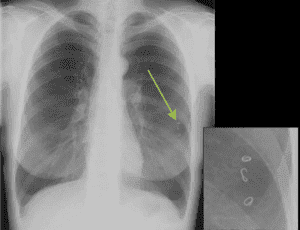

- При цистицеркозе личинка-цистицерк свиного цепня фиксируется в легочной интерстициальной ткани, и усиленно там размножается. Около нее создается фиброзная капсула, охваченная лимфоцитарной инфильтрацией, и образуются многочисленные круглые или овальные, диаметром 1 или 2 см, отдельные пузырьки. Вначале заболевания в прилегающей к очагам легочной паренхиме изменений не наблюдается, но затем развивается деформация структуры легочной ткани. Если пузырьки образуются под плеврой, то происходит очаговое уплотнение реберной и междолевой плевры. Когда же произойдет гибель цепня (через 2-3 года) очаги кальцифицируются.

Самый простой и достаточно надежный метод определения наличия паразитов в легких рентген. Рентгенографическое исследование позволяет обнаружить следы жизнедеятельности глистов, самих гельминтов, кисты, образующиеся при эхинококкозе.